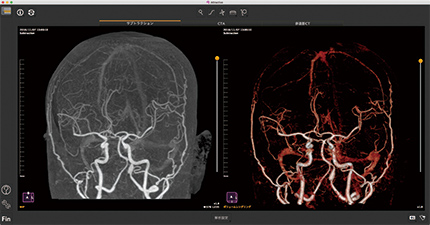

CT頭部サブトラクション

データ起動直後からフルオート処理、高速レジストレーションを搭載、フィルタ処理で骨を綺麗に消去。